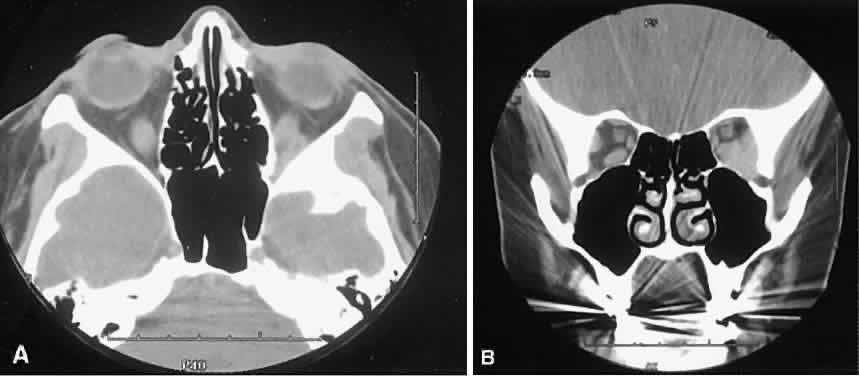

Nonspecific inflammatory dacryoadenitis shows enlargement of the lacrimal gland, which typically molds to the shape of the globe (Fig. 6). The adjacent bone is normal, and contrast enhancement of the gland usually is fairly homogeneous. Bilateral involvement may be apparent with certain conditions such as Sjogren's syndrome, sarcoidosis, lymphoma, or even Graves' orbitopathy, although enlarged EOM in the latter condition might make this a more obvious diagnosis.

Fig. 6. Nonspecific inflammatory dacryoadenitis. An isodense enlargement of the lacrimal gland is noted on axial (A) and coronal (B) views. Note the similarity to Figure 18.